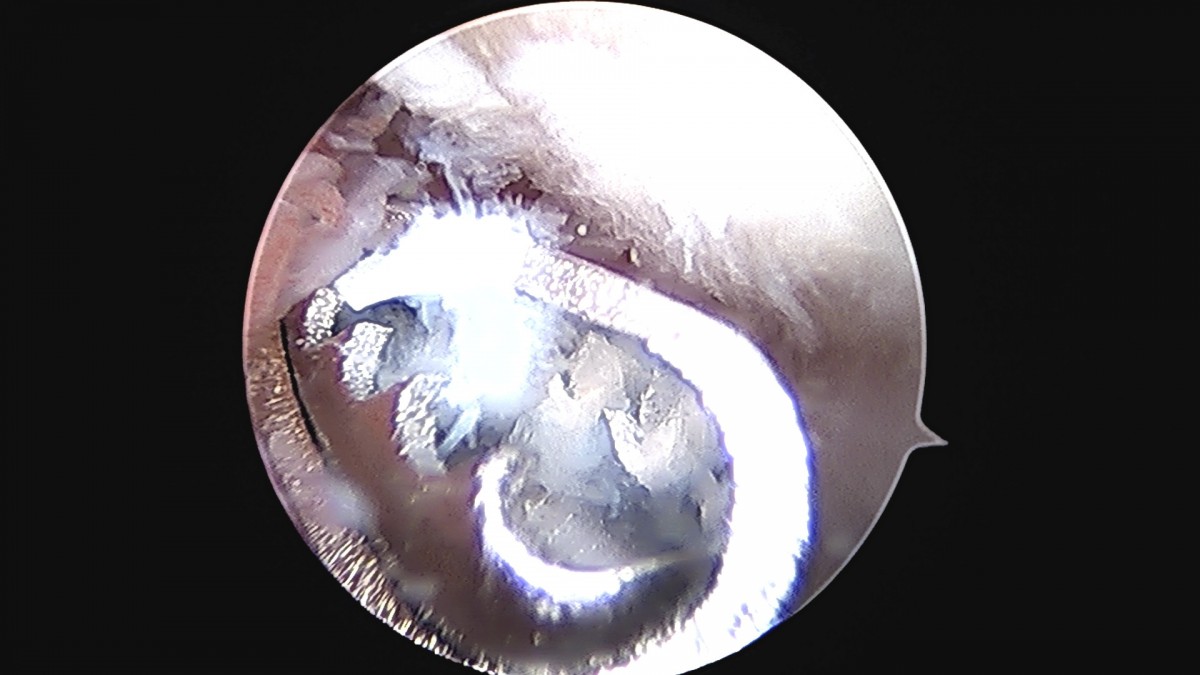

정지영원장님 손목 삼각섬유연골 복합체 봉합술 박현O 환자

작성자 최고관리자 댓글 0건 조회 778회 작성일 25-09-16 16:50